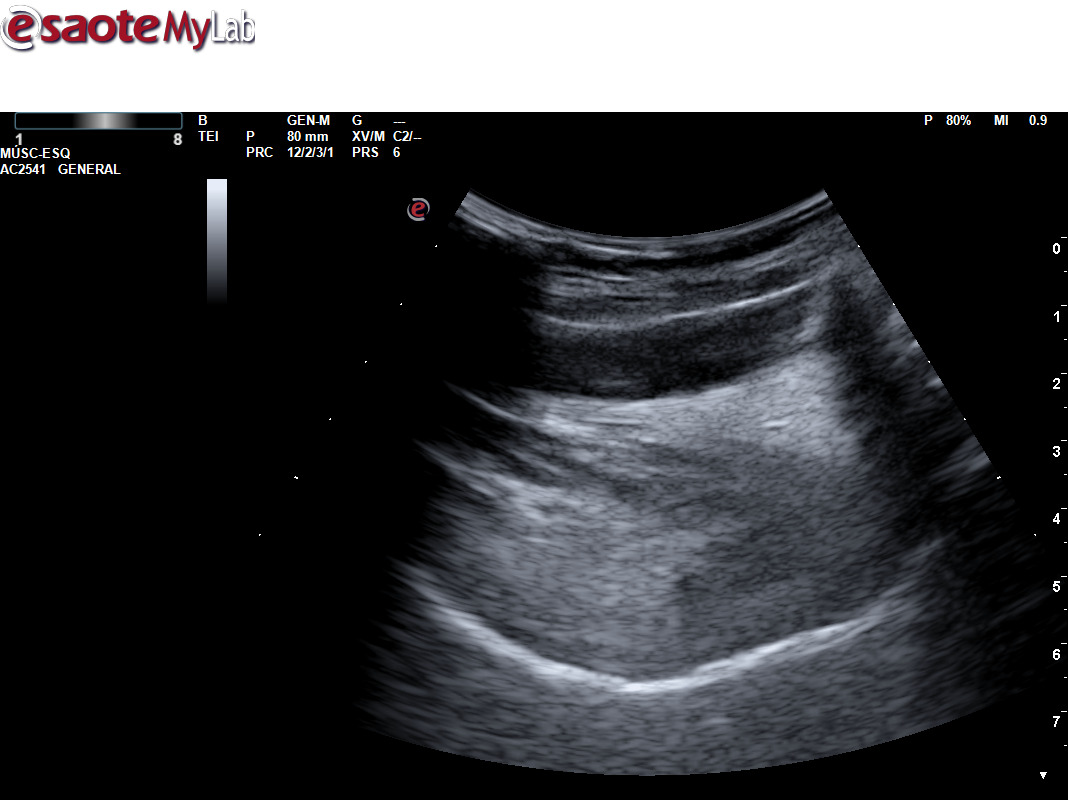

Para ello ponemos en práctica el protocolo específico de detección ecográfica de AOS, mediante la medición de la base de lengua y del espacio retrofaríngeo posterior para ver si cumple los criterios ecográficos establecidos, con las mediciones correspondientes que establecen la sospecha.